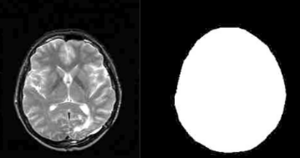

Atlas Guided Identification of Brain Structures by Combining 3D Segmentation and SVM Classification

Publication: MICCAI 2006, LNCS 4191, pp. 209–216, 2006. PDF

Authors: Ayelet Akselrod-Ballin, Meirav Galun, Moshe John Gomori, Ronen Basri, and Achi Brandt

Institution: Department of Computer Science and Applied Math, Weizmann Institute of Science, Rehovot, Israel and Dept. of Radiology, Hadassah University Hospital, Jerusalem, Israel

Background/Purpose: This study presents a novel automatic approach for the identification of anatomical brain structures in magnetic resonance images (MRI). The method combines a fast multiscale multi-channel three dimensional (3D) segmentation algorithm providing a rich feature vocab ulary together with a support vector machine (SVM) based classifier. The segmentation produces a full hierarchy of segments, expressed by an irregular pyramid with only linear time complexity. The pyramid provides a rich, adaptive representation of the image, enabling detection of various anatomical structures at different scales. A key aspect of the approach is the thorough set of multiscale measures employed throughout the segmentation process which are also provided at its end for clinical analysis. These features include in particular the prior probability knowl- edge of anatomic structures due to the use of an MRI probabilistic atlas. An SVM classifier is trained based on this set of features to identify the brain structures. We validated the approach using a gold standard real brain MRI data set. Comparison of the results with existing algorithms displays the promise of our approach.